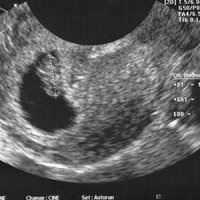

کریمی عنوان کرد: ماه پیش وزارت بهداشت دستورالعمل گایدلاینهای انجام سونوگرافی بارداری را به دانشگاه های علوم پزشکی ابلاغ کرد که به دنبال اعتراضات شدید جامعه رادیولوژی، وزارت بهداشت با قبول اشکالات ماهوی متعدد در این گایدلاینها اجرای آن را متوقف کرد.

وی گفت: چند روزی از این ماجرا نگذشته بود که وزارت بهداشت در اقدام نسنجیده دیگری بخشنامه ای با موضوع سونوگرافی سطح یک صادر کرد و تنش و التهاب جدیدی را باعث شد.

دبیر انجمن رادیولوژی ایران اظهارداشت: سونوگرافی کاری تخصصی است و نقش حیاتی در مدیریت درمان بیماران دارد آموزش آن یک دوره ٤ساله در محیط بیمارستانی و دانشگاهی میطلبد و قابل انجام بعد از گذراندن دورههای چند روزه و حتی ٢ و٣ ماهه نیست.